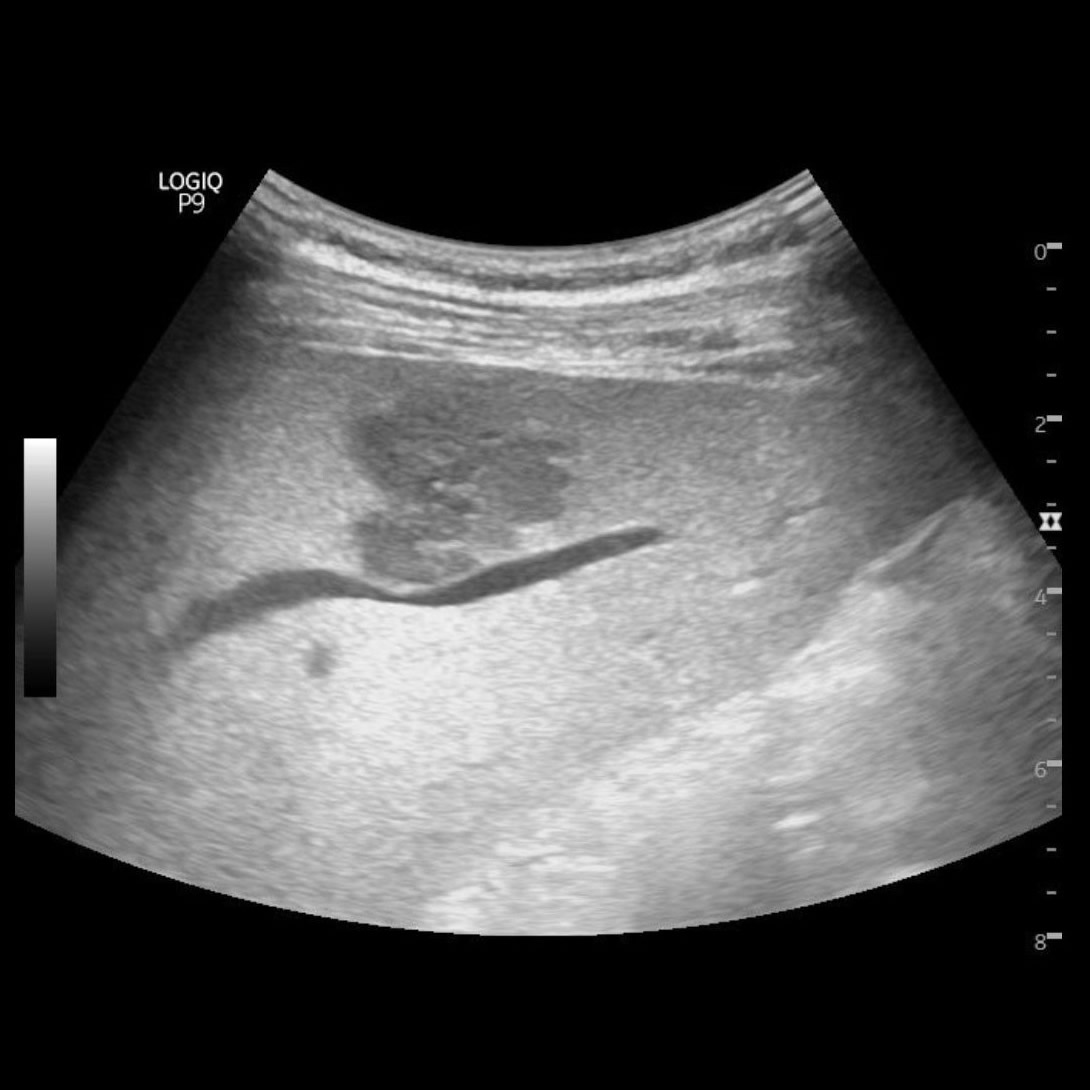

Agosto 2023. Clínica Reina Fabiola Masculino 40 años de edad HIV + Síndrome febril + pérdida de peso 18 Kg en los últimos 6 meses